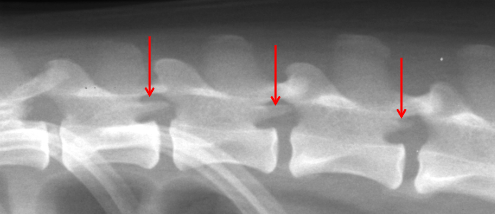

Cranial Costal Fovea

What ligament runs between the rib heads?

Intercapital Ligament

ID

Accessory Process

What is the attachment site of the crura of the diaphragm?

L3 and L4